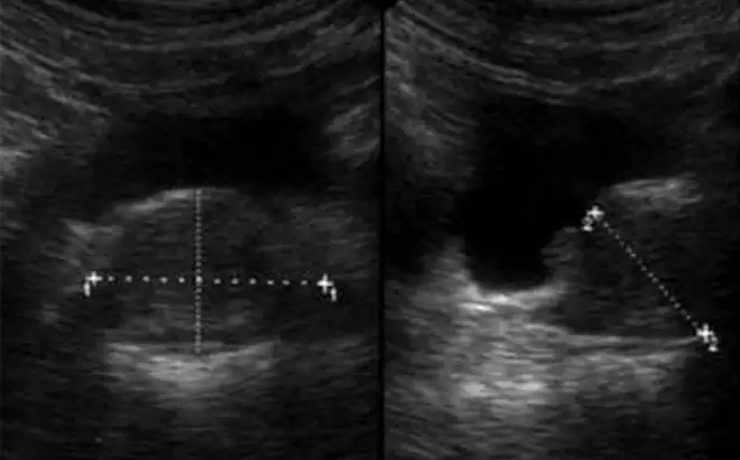

Introducción: El cáncer de endometrio es la segunda neoplasia ginecológica a nivel mundial ,más común en la perimenopausia , la incidencia es de 6 veces mayor en países desarrollados que en los menos desarrollados. La supervivencia en etapas tempranas es del 80%. Estudios de tamizaje Escrutinio a partir de los